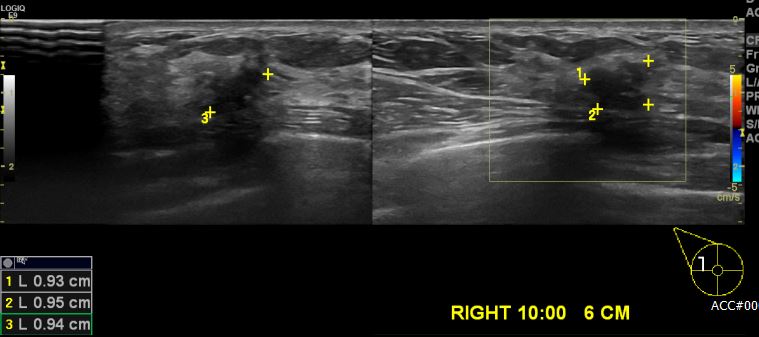

상기 환자 호르몬제 장기 복용하시는 50대 여성분으로 유방 초음파상 우측 10시 방향

5~6 cm 떨어진 거리의 혹 조직검사 시행하여 우측 침윤성 유관암 진단 되었습니다.